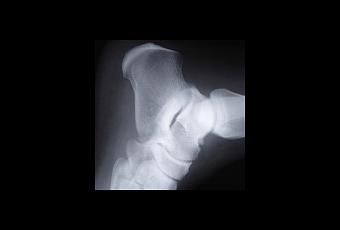

Le choix des implants prothétiques et les techniques opératoires dépendent de l’âge et de l’état général du patient, de ses antécédents et de la qualité de l’os.

Depuis plusieurs années, comme dans d’autres disciplines chirurgicales, on assiste à une chirurgie moins invasive avec diminution de la taille des incisions, préservation des tissus mous (tendons et muscles), grâce principalement à l’amélioration de l’instrumentation. De plus en plus de chirurgiens font appel à l’informatique dans la préparation de la chirurgie prothétique de la hanche et du genou: planification tridimensionnelle ,dans le but d’améliorer le positionnement des implants ou dans certains cas fabrication de prothèses sur mesure, mais la plupart du temps les prothèses standard sont parfaitement adaptées. Ces évolutions permettent le lever et la reprise précoce de la marche (jour opératoire ou lendemain), la reprise des activités de loisirs et sportives telles que le vélo, la marche prolongée et la natation dès le 3e mois, et la reprise des activités sportives telles que le ski, le tennis en double dès le 6e mois postopératoire environ. La course à pied et certains sports de contact doivent par contre être envisagés avec prudence.